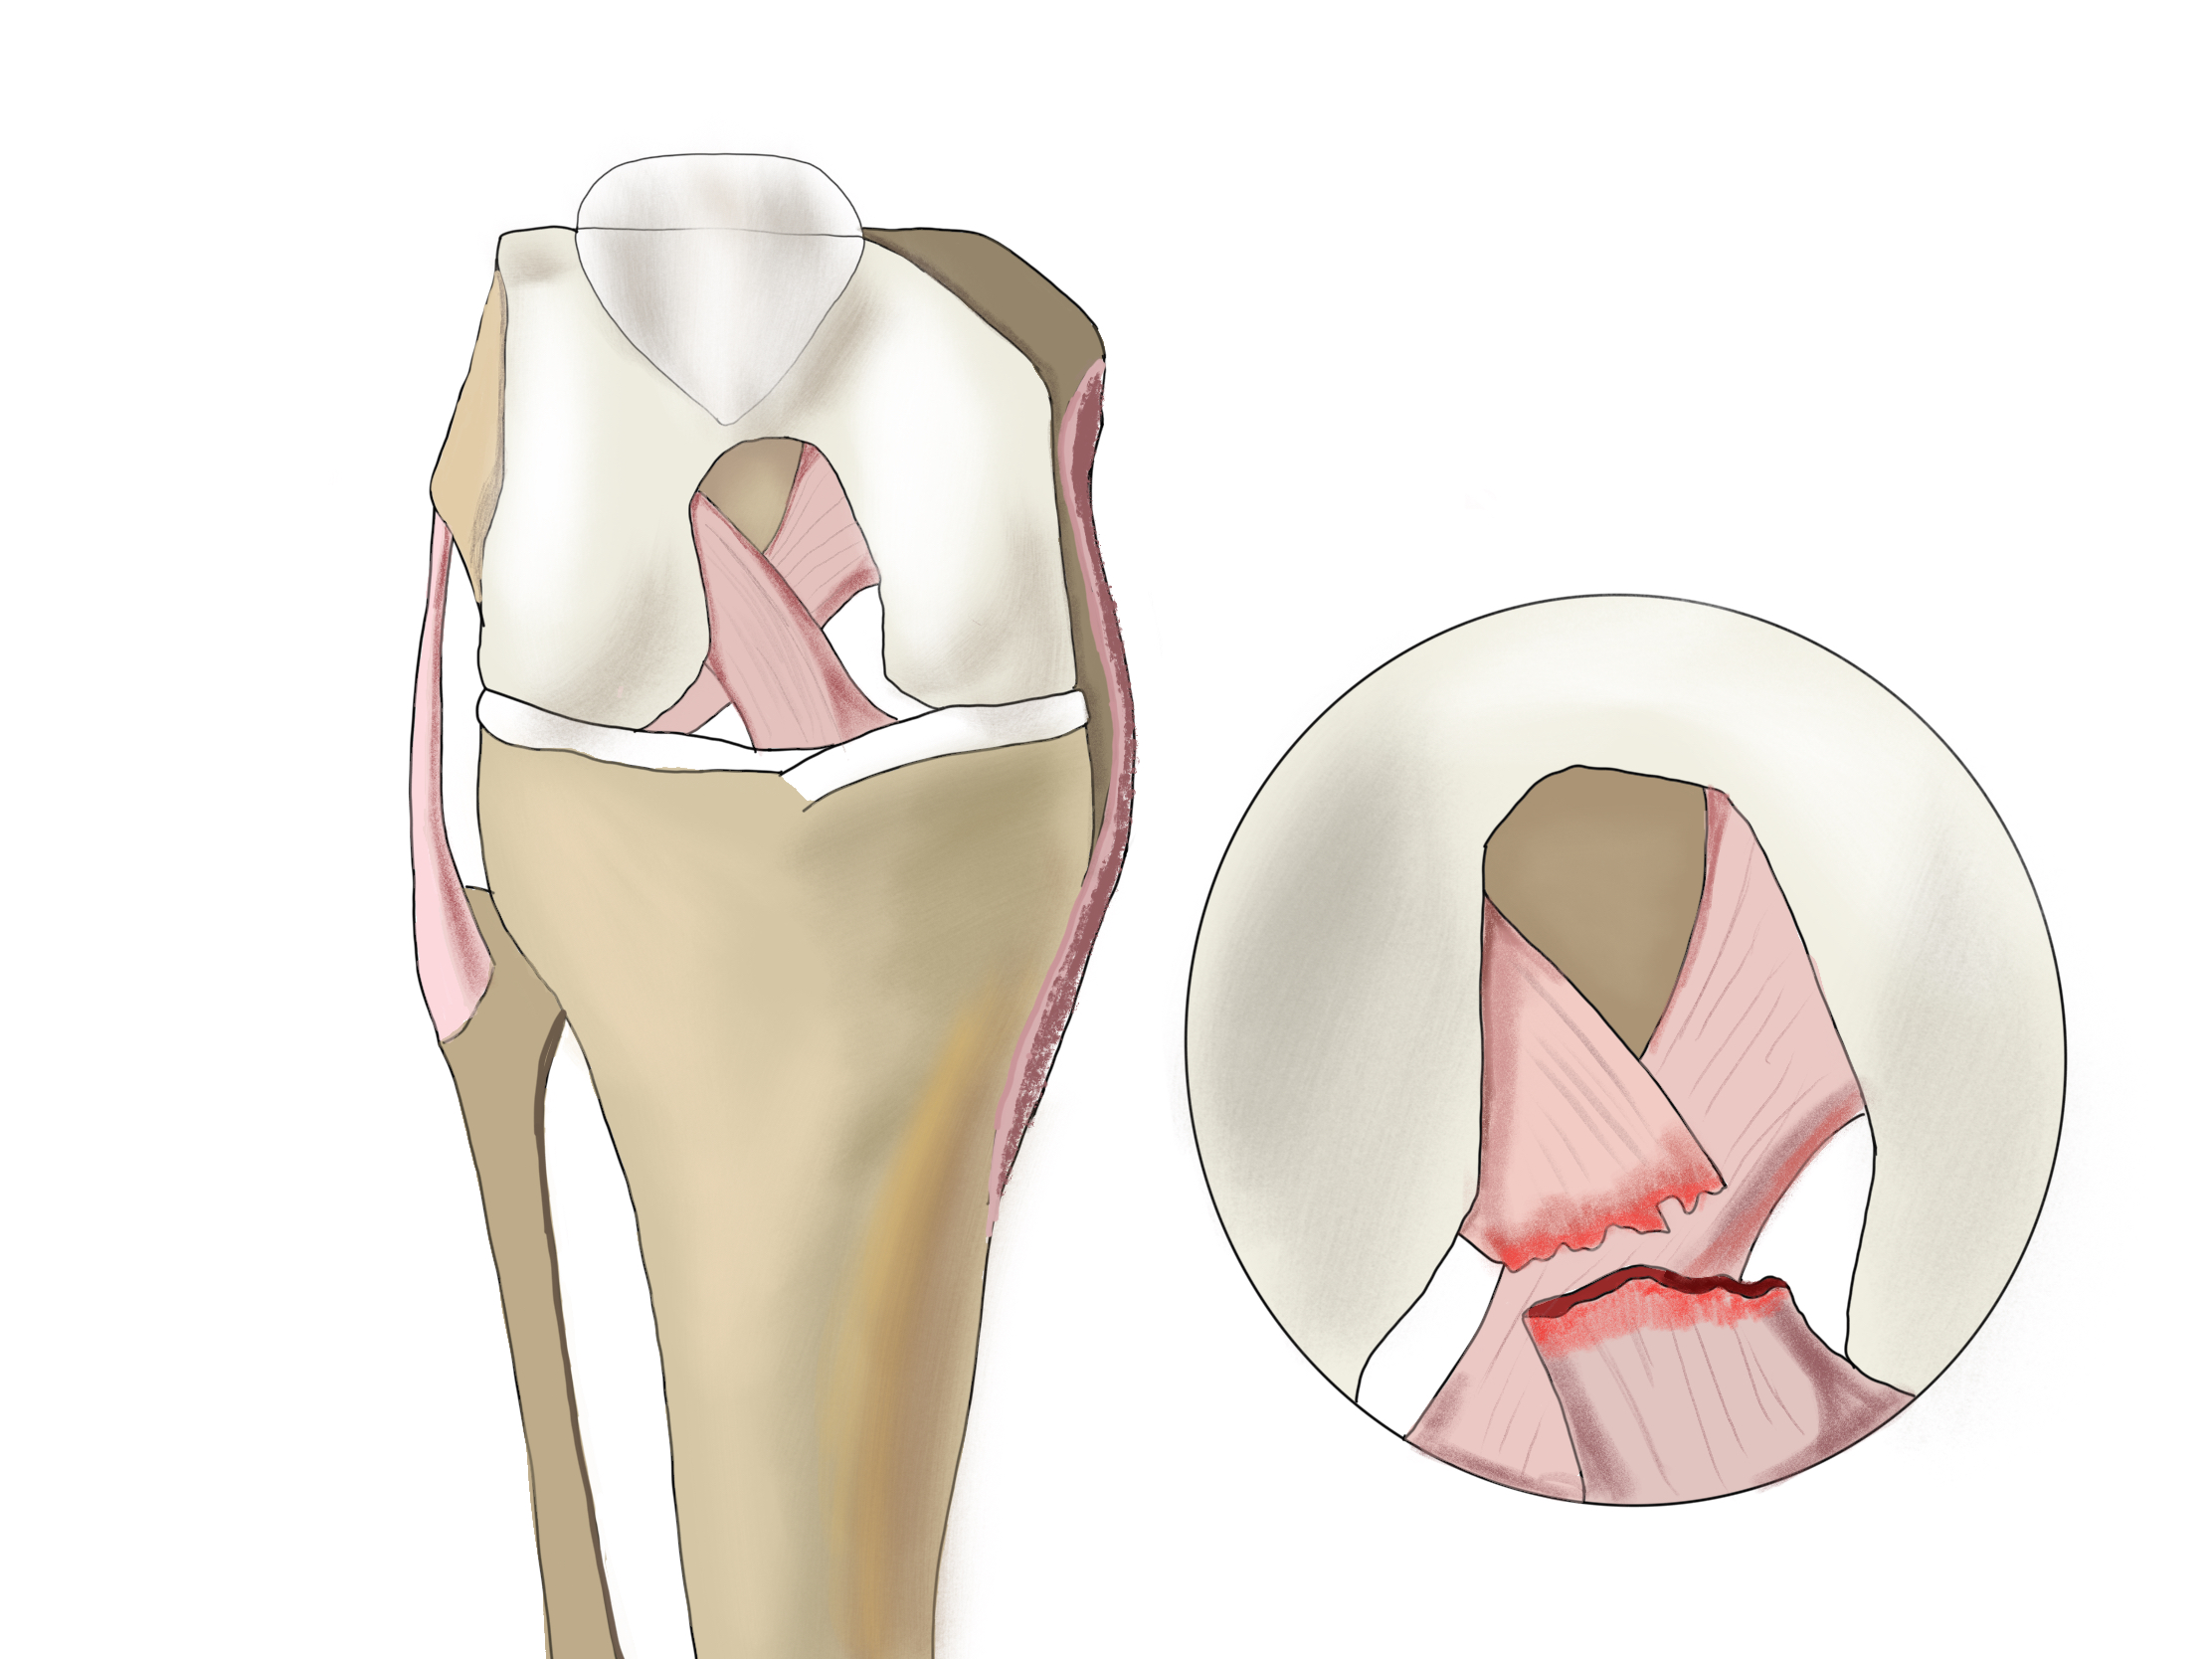

Проблемы с коленным суставом: флоттация и лечение